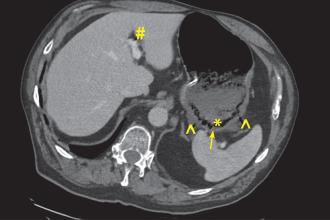

Clinical summary While vacationing in Mexico, a woman in her 70s presented to primary care with a 6-month history of B symptoms, worsening dyspnea, and new-onset back pain. Her medical history... Read More